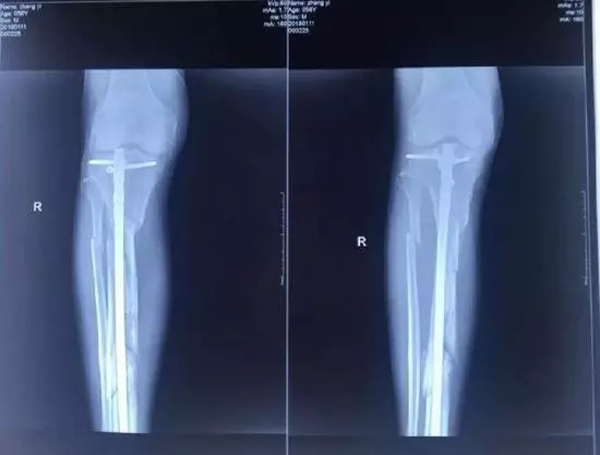

他興辦的廊坊市城南骨科醫(yī)院發(fā)展得越來(lái)越好,引起了原本是小股東的楊玉忠對(duì)醫(yī)院的覬覦。股東如果想要擴(kuò)大股權(quán),有許多正常的途徑,用合理合法的方式完全可以實(shí)現(xiàn)。但楊玉忠卻采取了最直接卻也最暴力的方式,不斷用欺騙、騷擾、干預(yù)人事等方式排擠張毅,使他在專心看病的同時(shí),疲于應(yīng)付,心理壓力極大,甚至在2017年10月18日,張毅被四名駕駛無(wú)牌豪華越野車的黑衣人打斷腿骨。即使是如此,當(dāng)?shù)睾趷簞?shì)力依然沒(méi)有放過(guò)張毅,不僅舊醫(yī)院被掏空占據(jù),新醫(yī)院也無(wú)法開張,200多醫(yī)護(hù)人員面臨衣食無(wú)著的困境。雖多方求助,對(duì)方依然逍遙法外,最終逼死了張毅。

資料圖